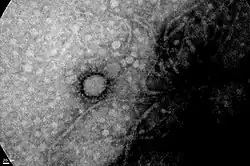

.jpg)

Argentine scientists developed a quick diagnosis test to detect the severe acute respiratory syndrome coronavirus 2 (SARS-CoV-2), approved by the National Administration of Medicines, Food and Medical Technology (ANMAT in Spanish). The test, called NEOKIT-COVID-19, allows to obtain results in almost an hour and it offers a high degree of sensitivity (which reduces the possibility of false negatives) and specificity (which minimises the probability of false positives).[135] This test allows testing RNA samples and does not require complex equipment (such as thermal cyclers).[136] It was expected that 10,000 tests would be produced within the first 10 days.[137][138] On 13 June 2020, a new announcement of another quick diagnosis test to detect the SARS-CoV-2 was made. Called ELA-chemstrip, it was developed by Argentine scientists from the National University of Quilmes and the National University of General San Martín.[139] Another SARS-CoV-2 diagnostic kit with RT-qPCR technology was approved in September 2020 by ANMAT, while a new kit under development (as of that date), would allow the joint detection of SARS-CoV-2 and the viruses that cause influenza.[140]